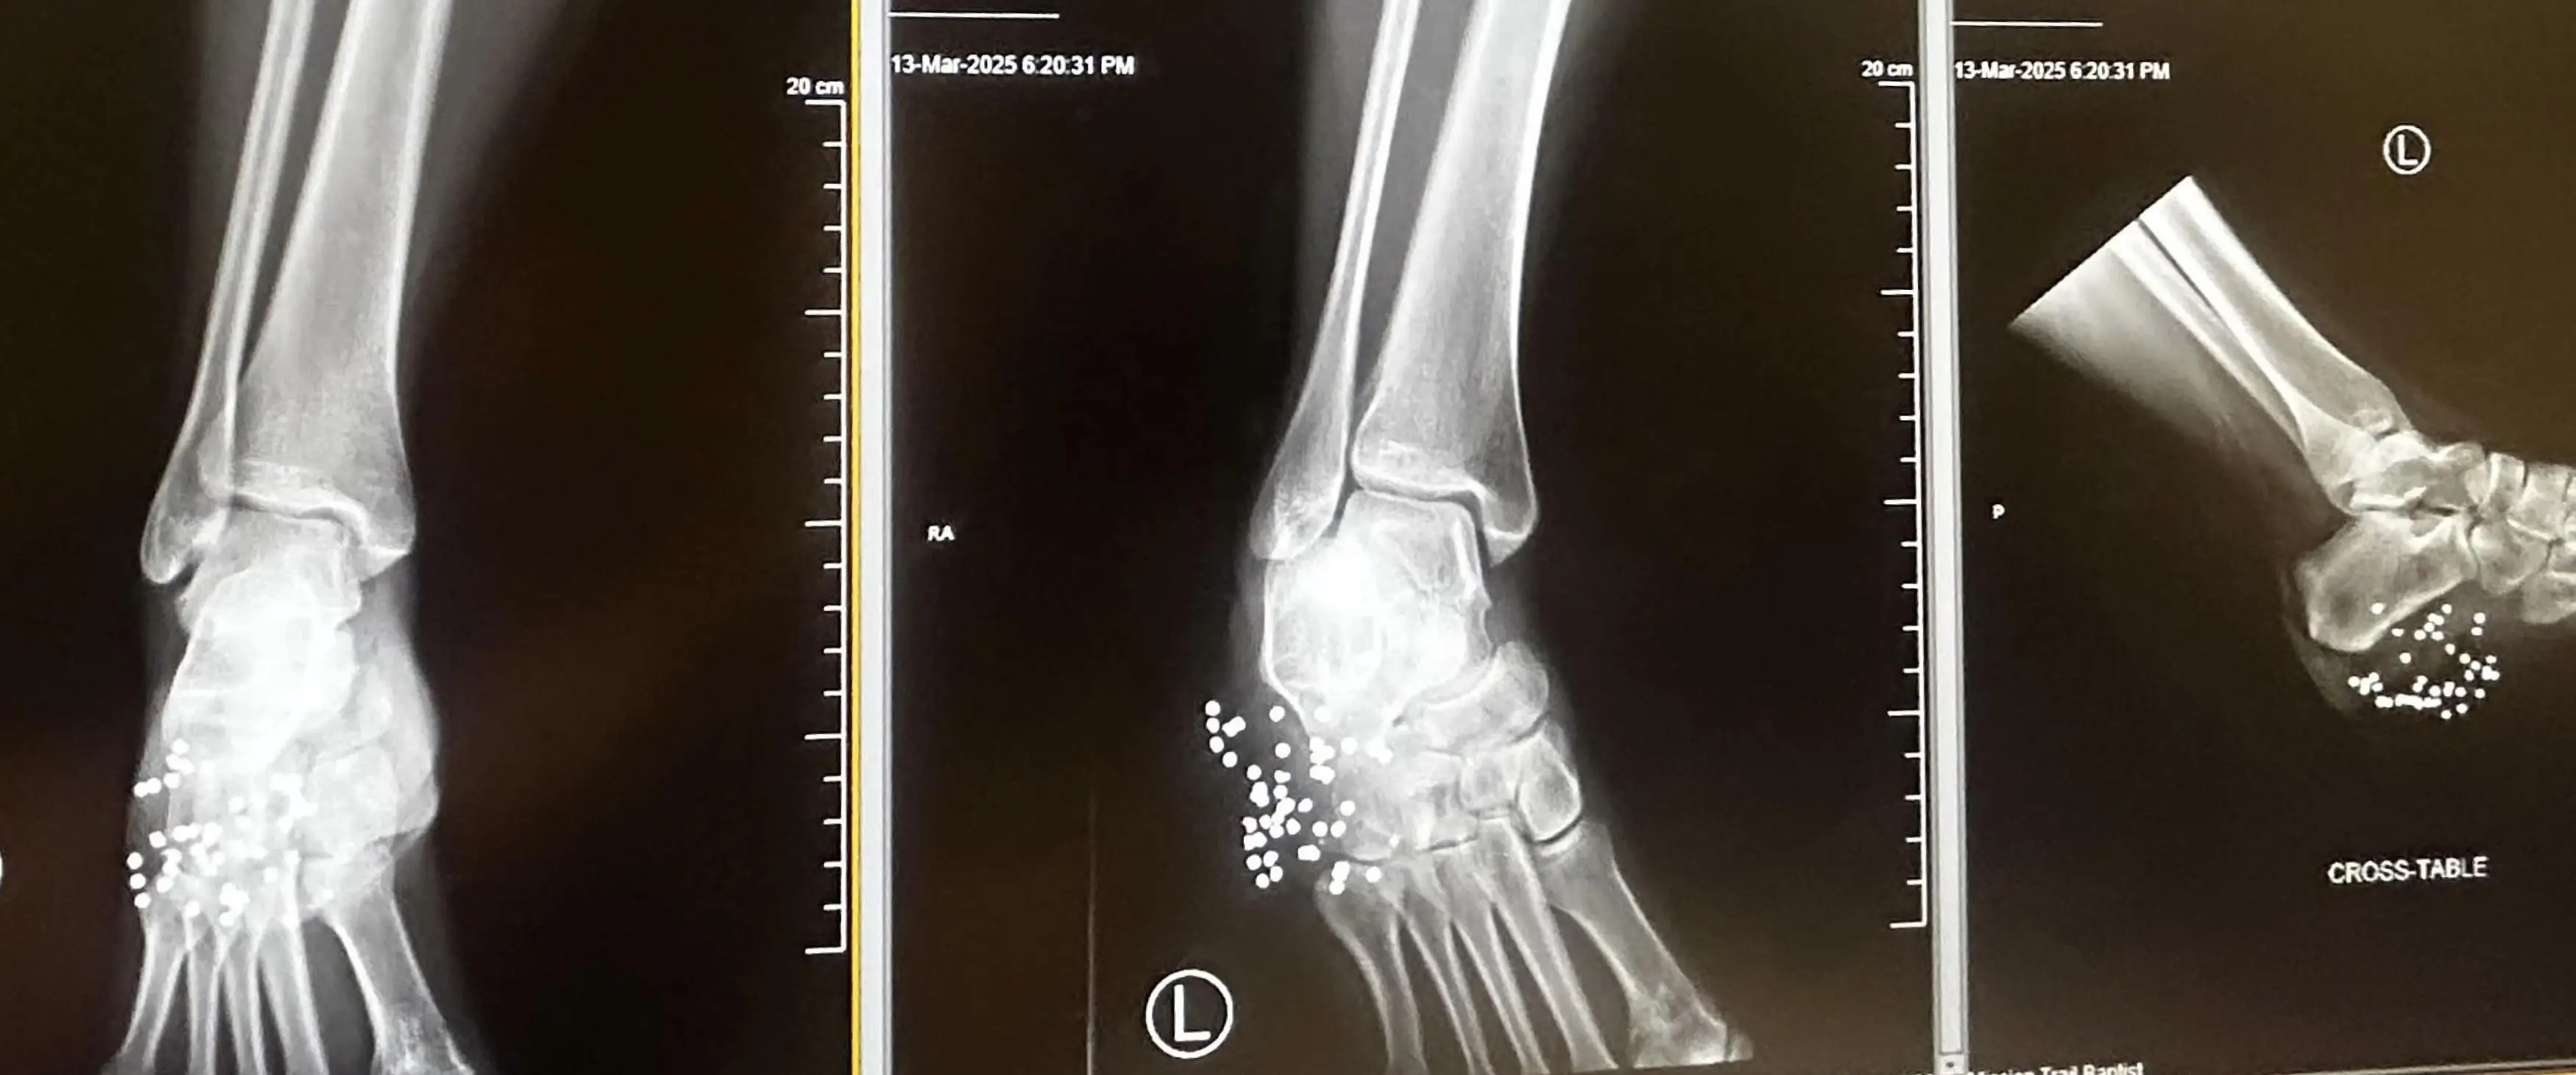

Hit with a reported 40 pellets, Marissa credits her Crocs shoes as to why her foot wasn't lost completely.

Doctors were able to retrieve 20 of the 40 pellets from her foot and Marissa is set to undergo a skin graft to help heal the wound left on her foot as a result of the operation.